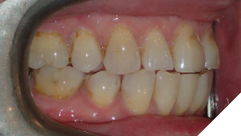

The majority of the orthodontic practices offer a period of “supervised retention” to their patients and communicates the customized retention recommendation with the patient’s general dentists. It is extremely important to work as a team to achieve long term clinical success in maintaining a functional bite and aesthetic smile. The general dentists continue to see their patients on a regular basis and have an opportunity to assess the orthodontic retainers and the bite after the supervised retention period is completed by the orthodontists. With great care, orthodontic retainers would serve for a long time (Fig. 1) without any major issues. However, in some cases, the failure to notice the clinical problems early on results in functional issues that would require a comprehensive orthodontic treatment to correct it (Fig. 2).

Fig. 1A

Fig. 1B

Fig. 1C